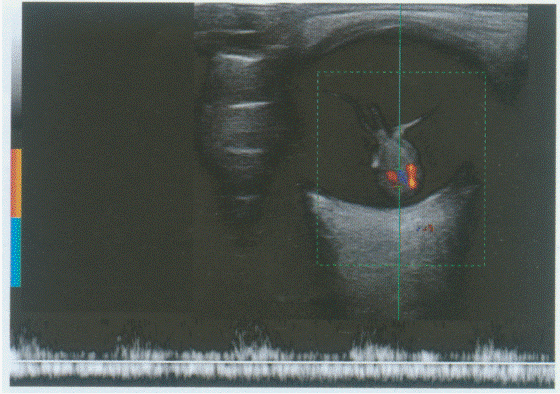

43、单项选择题

颈部扫查:请指出图1中测量为0.31cm的管径,彩图85(1)所指,彩图85(2)PW取样容积取样处分别是颈部哪条血管()。

A.椎动脉

B.甲状颈干动脉

C.颈总动脉

D.锁骨下动脉